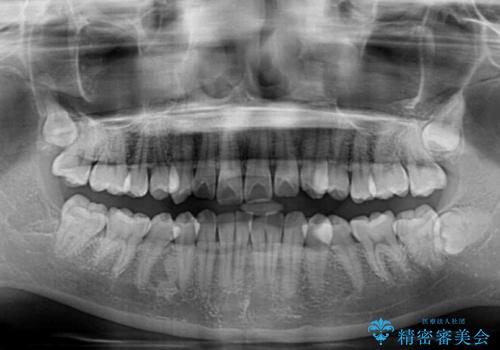

- 上下前歯のデコボコとディープバイトを気にして来院された患者様です。

歯列全体に叢生があり、舌の突出癖が認められたため、突出癖が改善されない場合には口元が突出するリスクが考えられました。

なかなか舌の突出癖が改善できず、上下前歯が非接触となる期間が長く続きました。

アンカースクリューの活用と、舌のトレーニングを何度も指導し、出っ歯になることなく無事に治療を終えることができました。